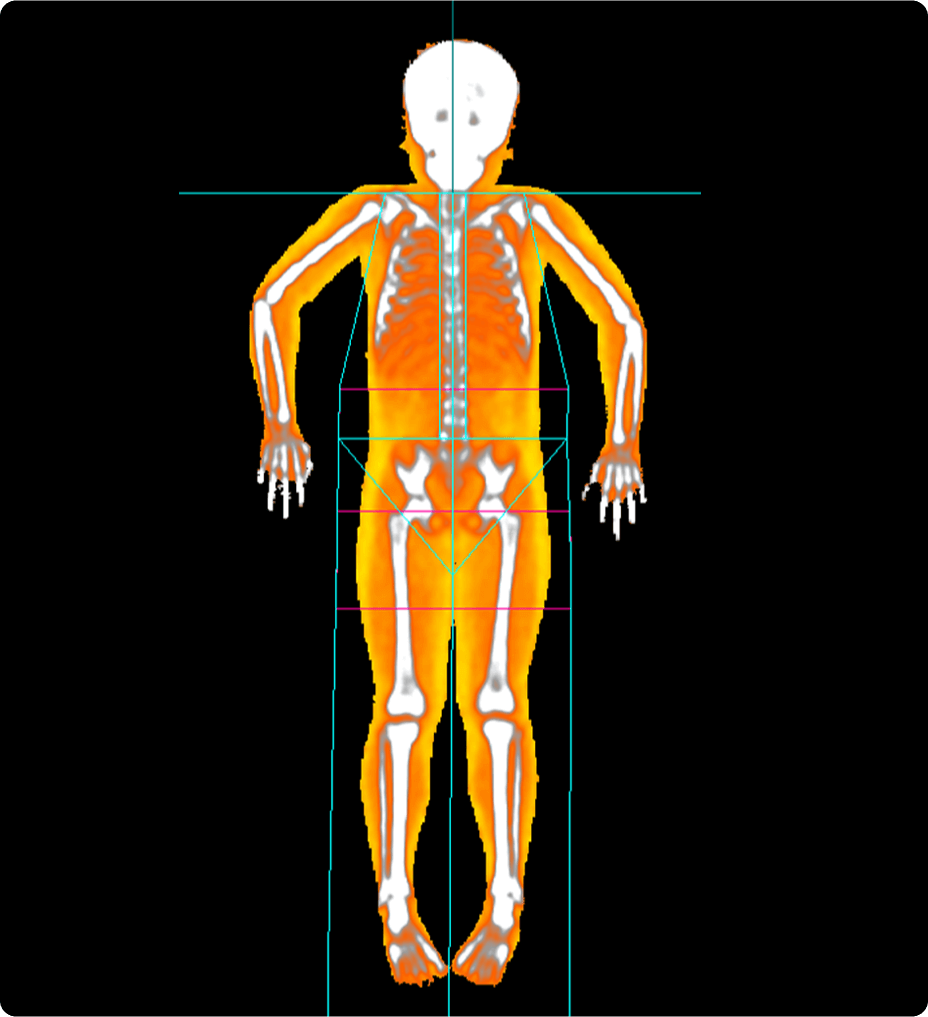

Nuestra cámara Xtream utiliza tecnología de detección precisa en tiempo real para generar un modelo 3D del cuerpo del paciente. A continuación, mediante nuestro algoritmo de aprendizaje profundo, Revolution Advance localiza el centro del rango de exploración y lo alinea automáticamente con el isocentro del túnel. Con un solo clic, el posicionamiento automático utiliza toda esta información para centrar automáticamente al paciente sin necesidad de intervención.

Esta tecnología inteligente proporciona tiempos de exploración más cortos, lo que hace que la experiencia de exploración sea más cómoda para sus pacientes. También ayuda a optimizar la dosis, mejora la calidad de la imagen y proporciona una mayor uniformidad en la exploración.